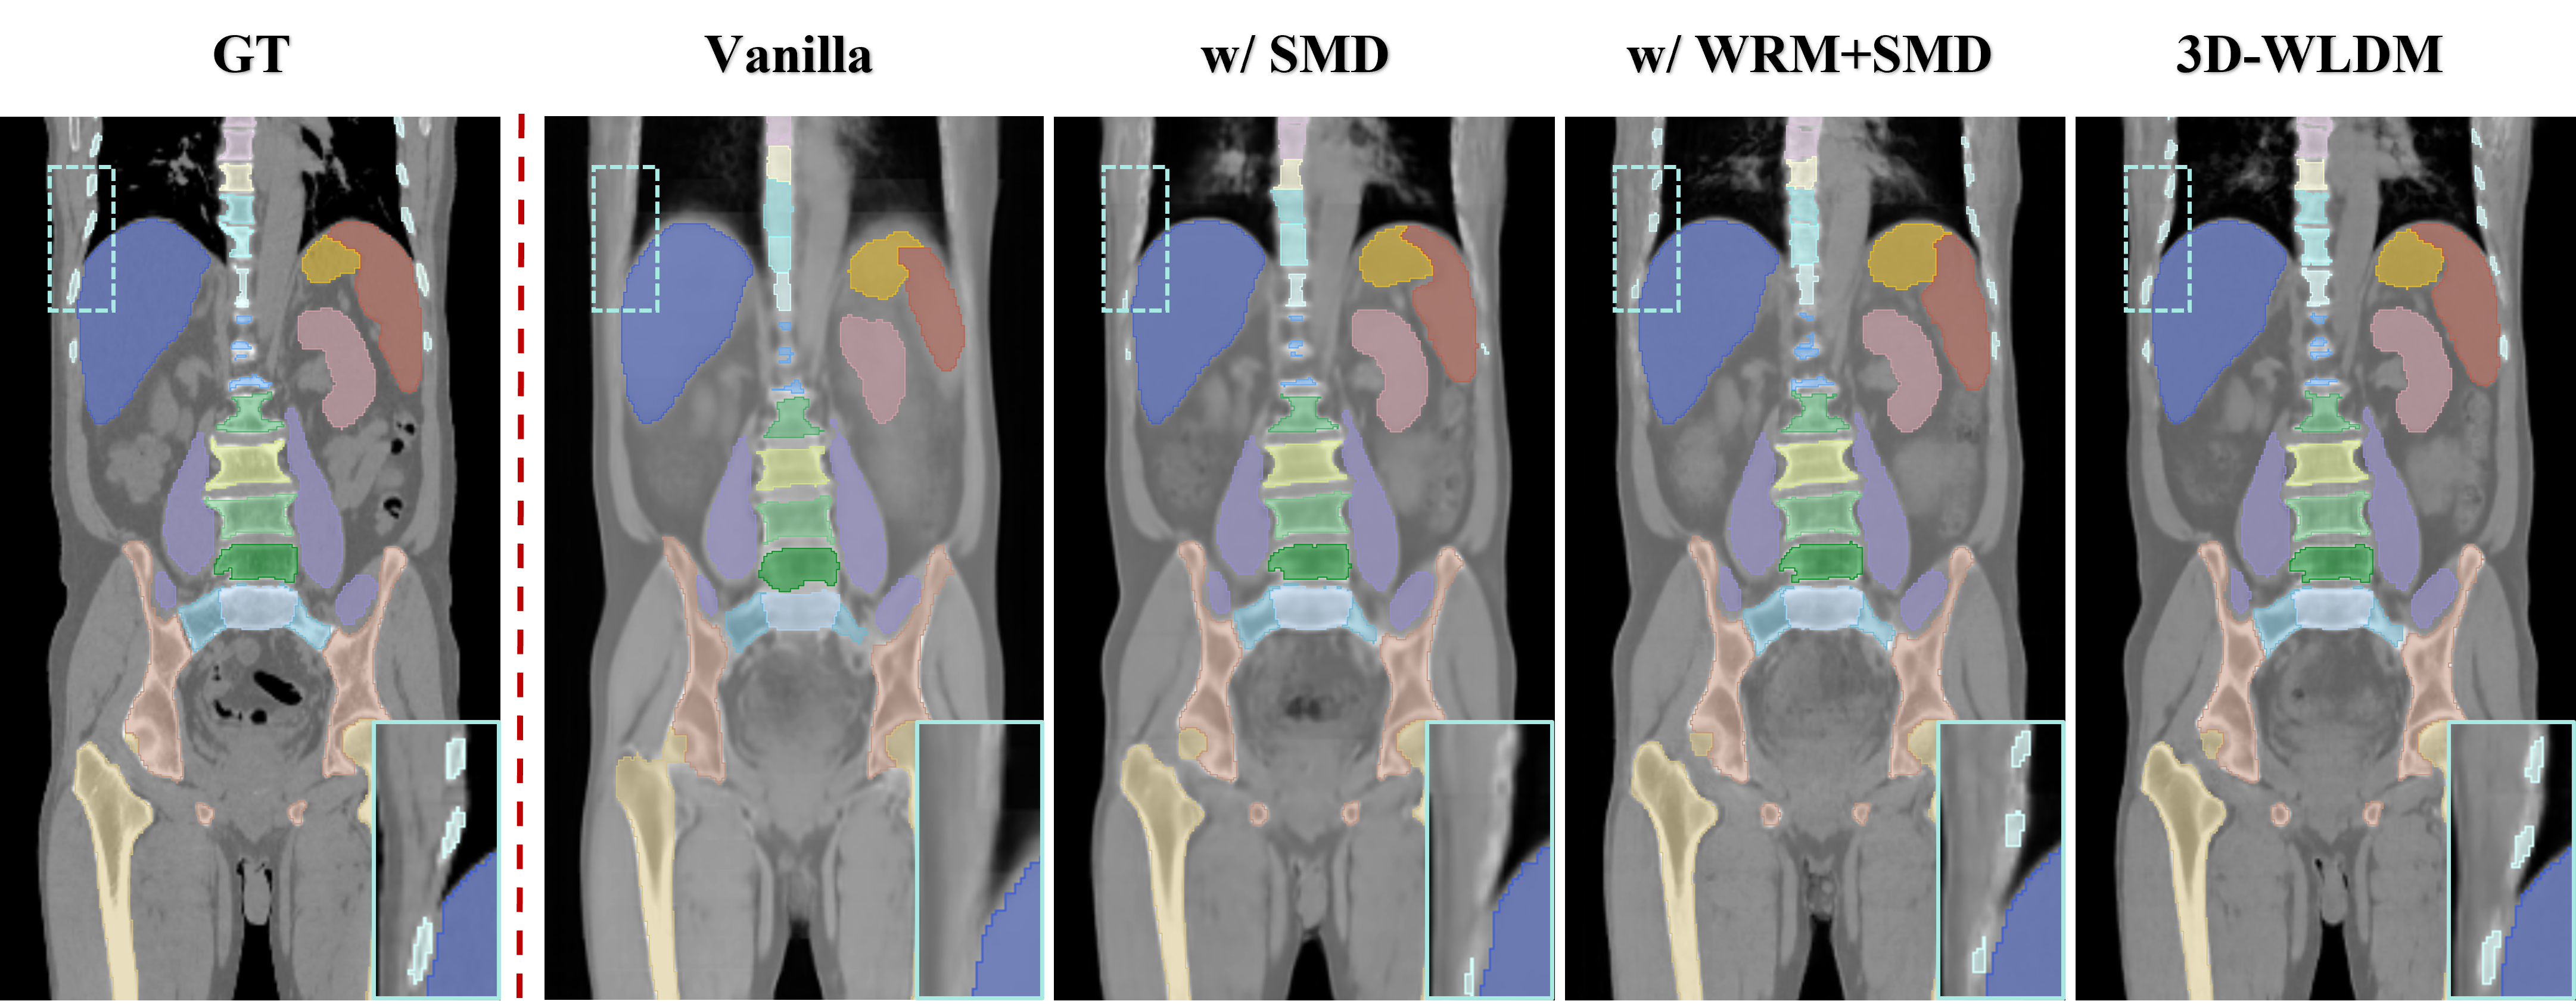

IV-C2 Semantic segmentation Analysis

To assess the downstream utility of the synthesized CT images produced by different ablation variants, we conducted a segmentation study using the publicly available TotalSegmentator tool [43], which automatically delineates major anatomical structures. Segmentation performance was quantified using the Dice Similarity Coefficient (DSC), with results for representative organs and skeletal structures summarized in Table III. Ours model demonstrated substantial improvements in segmentation accuracy compared to the Vanilla, with DSC gains of 17.2% for the spleen, 12.6% for the kidneys, 4.1% for the liver, 15.4% for the stomach, and 10.3% for vertebrae. These improvements reflect enhanced anatomical fidelity and structural consistency in the synthesized CT volumes, underscoring the clinical relevance of the proposed framework.

To further illustrate the key contributions of each model component, Fig. 8 presents qualitative comparisons of segmented anatomical structures across model variants. The introduction of the SMD module leads to markedly improved spatial alignment of structures such as the femur, reflecting better retention of global anatomical geometry. The addition of WDM and the DSCA module respectively yields enhanced delineation of fine anatomical details, particularly in complex bony regions such as the ribs and vertebrae. Together, these findings demonstrate that improved synthesis quality directly translates to higher segmentation performance, highlighting the potential of 3D-WLDM to support clinically relevant tasks that depend on structurally accurate CT representations.